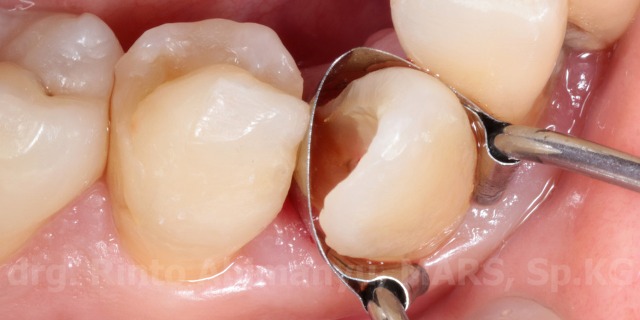

Keadaan awal gigi 43

Gigi 43 mengalami karies dan sudah terlihat perforasi ke kamar pulpa, perkusi negatif, dan respon dingin menunjukkan positif. Kemudian dari ronsen terlihat seperti ini..

Pemakaian matriks pada pembuatan artificial wall

Matriks yang saya pakai adalah saddle matrix dengan spring clip, matriks ini cukup murah dan mudah penggunaannya… sejawat harus punya nih.. cieee promosi 😛